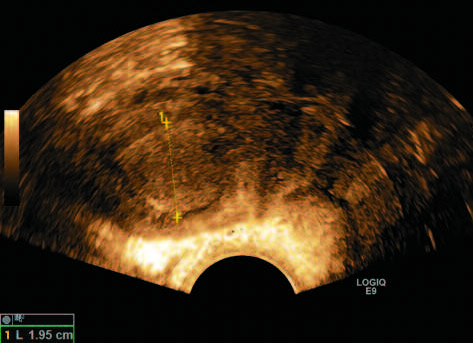

Многие исследования подтверждают данные A. Timmermans и соавт. В частности, исследование A. Wong и соавт. с участием женщин с ПМК показало, что пороговое значение толщины эндометрия 3 мм имеет чувствительность 97% и специфичность 45,3%; значение 4 мм имеет чувствительность 94,1% и специфичность 66,8%, а значение 5 мм имеет чувствительность 93,5% и специфичность 74% для выявления РЭ (рис. 1, 2) [30].

Рис. 2. Пациентка А., 64 года, постменопауза 20 лет. ПМК. Толщина эндометрия – 19 мм. РЭ (собственные данные).